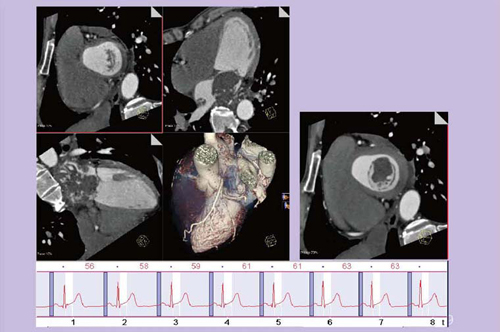

図6は,超音波検査で左房粘液腫が疑われた症例で,緊急手術となったため,外科からの依頼で術前に冠動脈評価を行った。粘液腫が嵌頓しそうになっており,周辺にもかなり侵襲していることがわかる。血管成分も多く,悪性が強く疑われた。動画もスムーズに観察することが可能であり,形態から血管成分も含めた腫瘍の性状まで評価できるため,CTのみで外科医に対して十分に有用な情報を提供できる。

図6 47歳,男性,心臓腫瘍